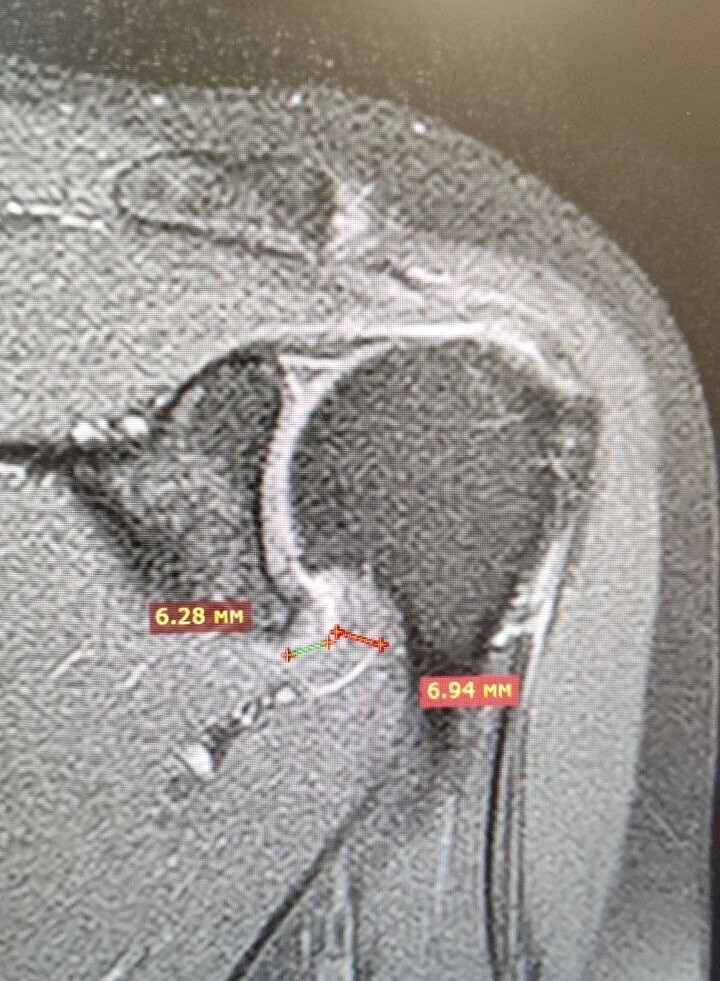

Вот такое плечо нам привезли из Италии.

Адгезивный капсулит, или с-м замороженного плеча.

Признаки этого заболевания можно увидеть на МРТ, утолщение капсулы сустава, с формированием отека, самое удобное смотреть в этом месте (отмечены размеры).